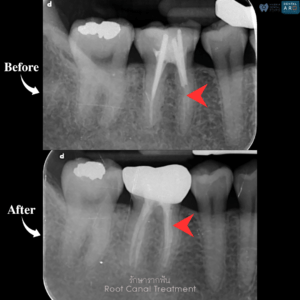

รักษารากฟัน

คือ การรักษาฟันที่เกิดการอักเสบและติดเชื้อภายในโพรงประสาทฟัน และเนื้อเยื่อรอบปลายรากฟัน อันมีสาเหตุมาการอักเสบและติดเชื้อภายในรากฟัน โดยทันตแพทย์จะทำการทำความสะอาดและใส่ยาในคลองรากฟัน และทำการอุดรากฟันเป็นขั้นตอนสุดท้าย การรักษารากฟันจะช่วยเก็บรักษาฟันให้สามารถคงอยู่ในช่องปากต่อได้ โดยไม่ต้องถอนฟันและไม่ต้องใส่ฟันทดแทน